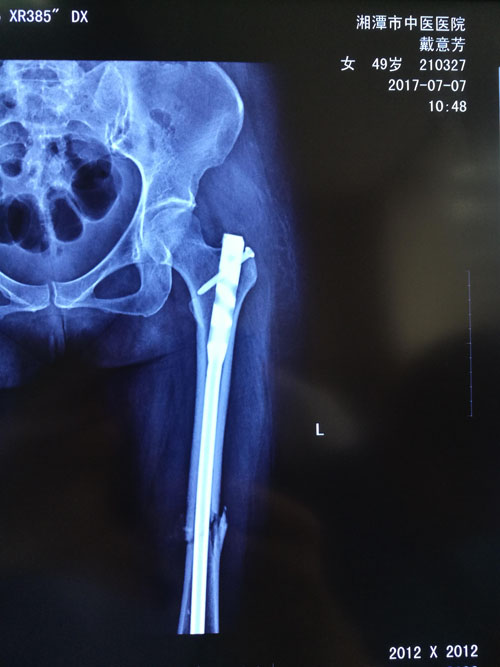

典型病例:閉合復位髓內釘治療股骨骨折,創(chuàng)傷小、出血少,骨折愈合快。